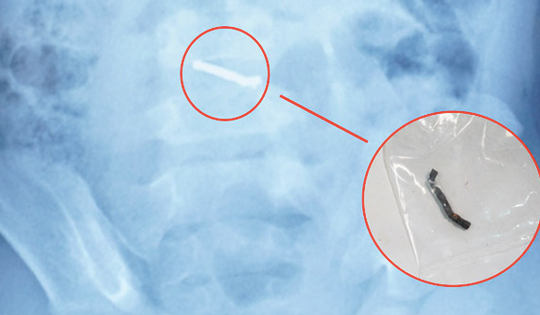

Nam châm đồ chơi dính chặt trong dạ dày bé trai

Bé Hoàng 4 tuổi vô tình nuốt đồ chơi có nam châm, ảnh chụp X-quang cho thấy dị vật vùng bụng trái.